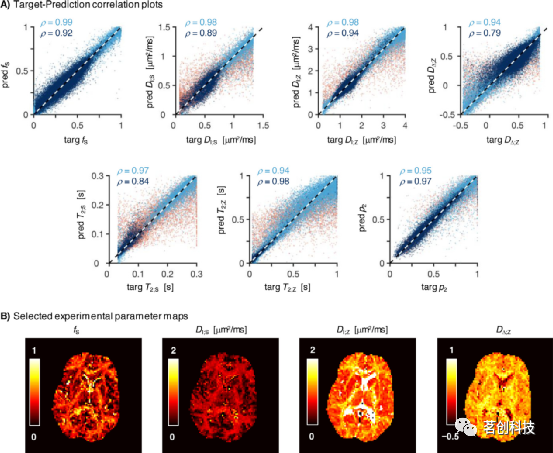

旋转不变性微观结构特征的神经网络拟合

图5A显示,使用旋转不变量训练SNN会导致目标参数和估计参数之间的相关性略强(与图2的散点图相比)。当DΔ;Z值较小时,精度有了相当大的提高,此时完整SMR模型(见图2)中观察到的常量DΔ;Z≈0.3行为不再存在。将旋转不变性(RotInv)网络应用于看不见的体内Sl={0,2}数据集会产生具有解剖学合理对比的参数图(见图5B)。可以看到,RotInv DΔ;Z图具有更平滑的外观,并且比其非旋转不变SMR对应图更好地界定了皮质/非皮质实质(将图1的第四列与图5B进行比较)。

图5.旋转不变(RotInv)模型的神经网络拟合产生了强目标估计相关性和合理的映射。